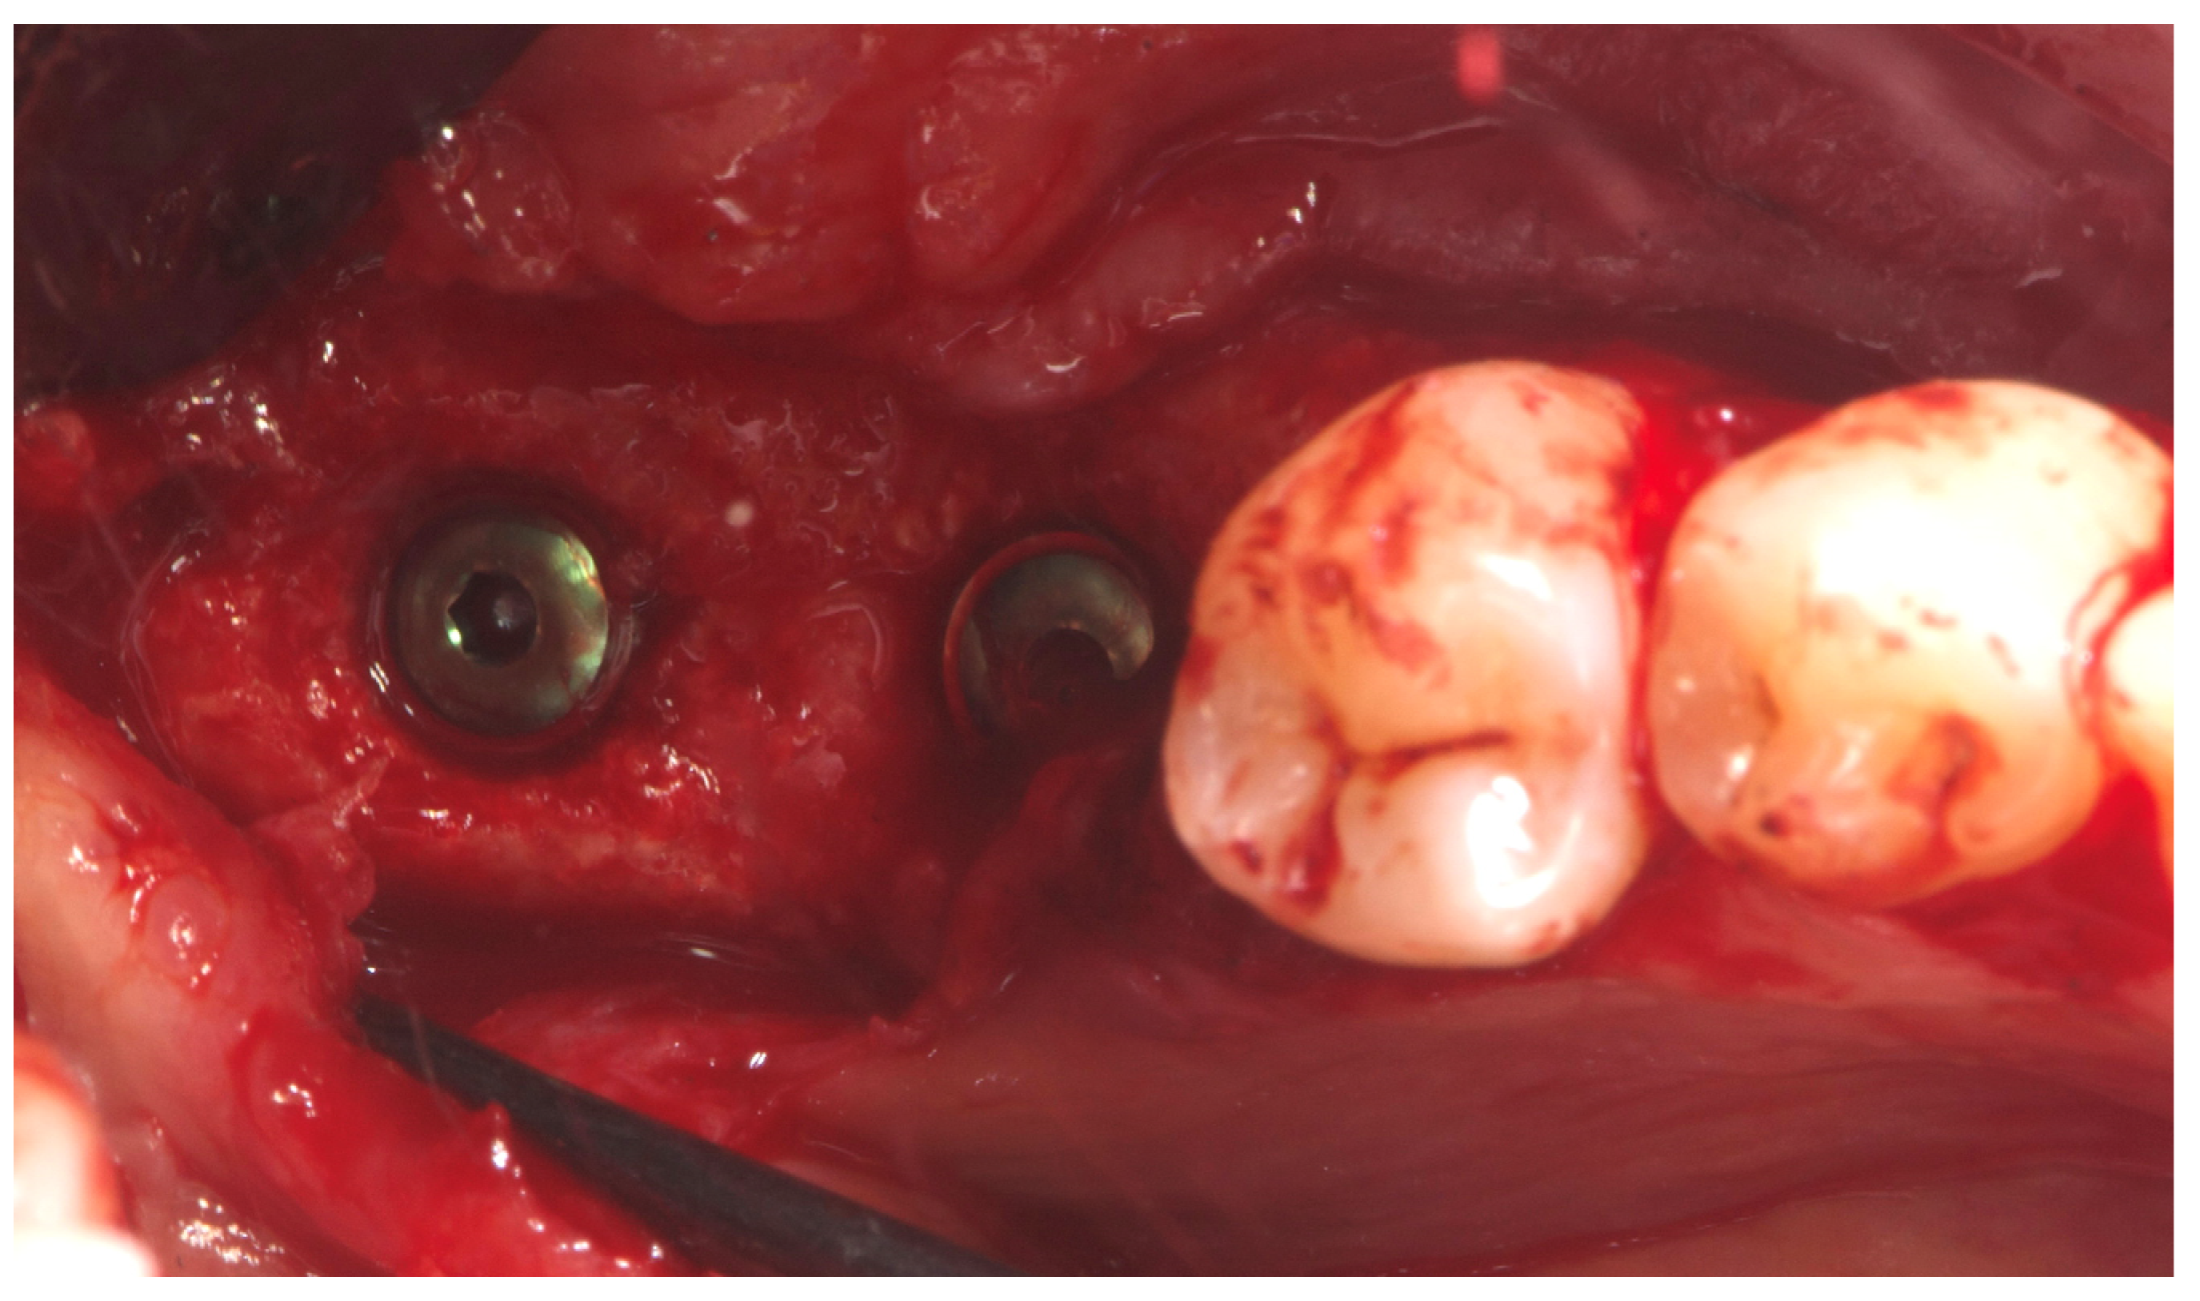

2. Case Summary